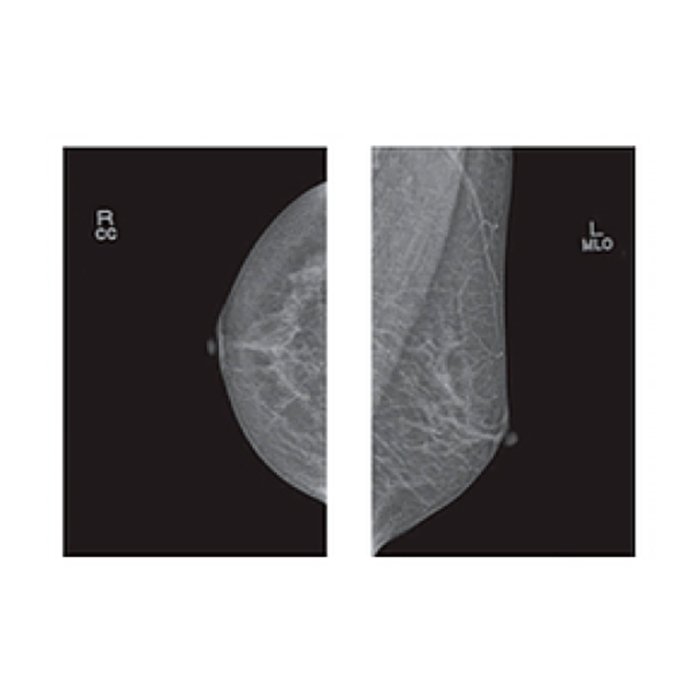

Маммограф Pinkview-RT аналоговый Bemems

Аналоговый маммограф Pinkview-RT (Bemems)

Аналоговый маммограф Pinkview-RT от компании Bemems — это надежное и проверенное решение для проведения скрининговых и диагностических исследований молочных желез. Аппарат предназначен для получения высококачественных рентгеновских снимков (маммограмм), которые являются основным инструментом раннего выявления патологий, включая онкологические заболевания.

- Высокое качество визуализации: Мощный рентгеновский трубчатый блок с молибденовым анодом и автоматическим выбором экспозиционных параметров гарантирует получение четких и информативных снимков с высокой контрастностью мягких тканей.